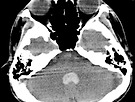

ICH, IVH cas..

JYW(전대-정영원) 15.06.21상기환자 HTN History 가지고 있는 환자이고 ..